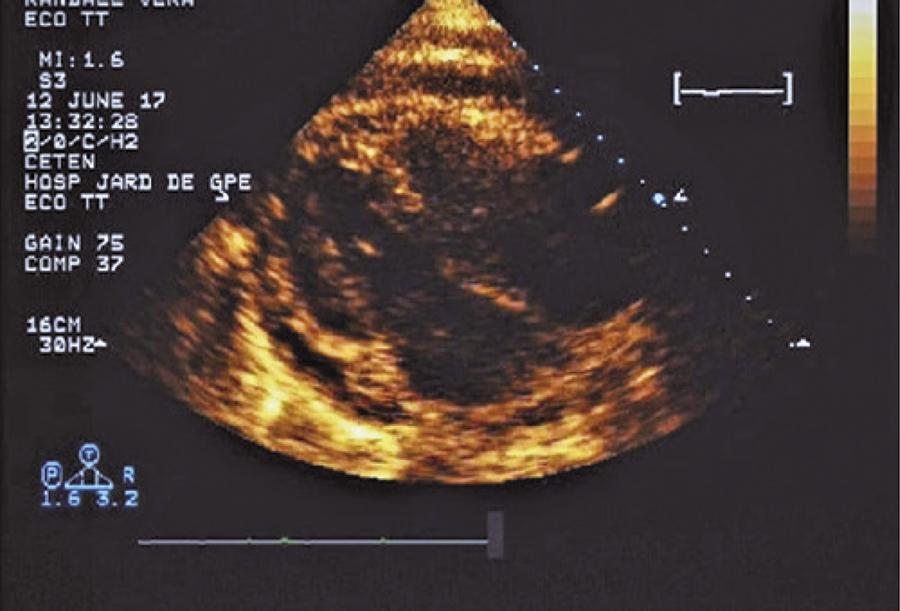

Figure 2

Global pericardial effusion observed by echocardiogram.